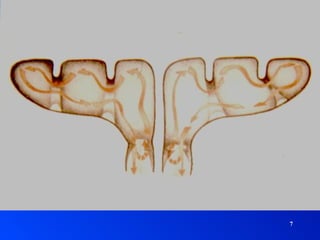

SINUSITIS AGUDA FactoresPredisponentes LOCALES Ostium Interrelación de senos Neumatización VECINOS Fosas Nasales Cavum Piezas dentarias GENERALES ETIOPATOGENIA

SINUSITIS AGUDA Factores Predisponentes LOCALES Ostium Interrelación de senos Neumatización VECINOS Fosas Nasales Cavum Piezas dentarias GENERALES ETIOPATOGENIA